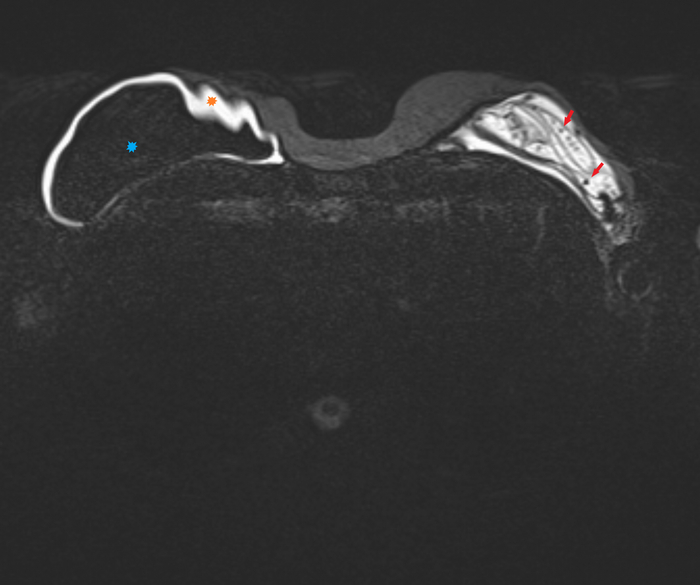

Пациентка, 64 года, перенесла двустороннюю мастэктомию (удаление обеих молочных желёз) по поводу рака 14 лет назад с пластикой с обеих сторон двухкамерные имплантами. Сейчас клинически подозревают фиброз капсулы и возможно разрыв левого импланта. Для подтверждения диагноза провели МРТ молочных желёз (только нативную часть протокола, т.е. без в/в введения контрастного вещества, от которого пациентка отказалась).

Начнём с краткого обзора здорового импланта:

Т2-взвешенное изображение

где центрально расположена камера, заполненная физ.раствором (голубой цвет), на периферии - камера, заполненная силиконом (красный цвет), и отграничено это всё фиброзной капсулой, которой тело старается отграничить инородный объект (пунктирная линия):

если мы сравним правый имплант с левым, то разница очевидна, тут не надо быть рентгенологом, чтобы понять что что-то тут не то, а именно сам имплант меньше, интенсивность сигнала иная (цвет более тёмный) + видны какие-то линии внутри импланта (красные стрелочки):

Линии эти - так называемый признак "лингвини" (или по-английски linguine sign), т.к. похожи они на одноимённую итальянскую пасту лингвини:

и являются ни чем иным как спавшимися стенками камер имплантов, что указывает на внутрикапсульный (в пределах образовашейся фиброзной капсулы) разрыв импланта, но без свободного выхода содержимого в окружающие мягкие ткани.

Интенсивность сигнала поменялась из-за того, что физ.раствор частично смешался с силиконом, и вследствие этого определяются пузырьки физ.раствора в силиконе - т.н. признак "салатного масла" или "salad oil sign" (капли, как при добавлении масла в воду):

которые я отметил красными стрелочками:

и на секвенции с подавлением воды, которая становится на картинке "чёрной" (синяя звёздочка), а силикон остаётся "белым" (красная звёздочка):

Имплант, соответственно, больше не жизнеспособен и его следует заменить.